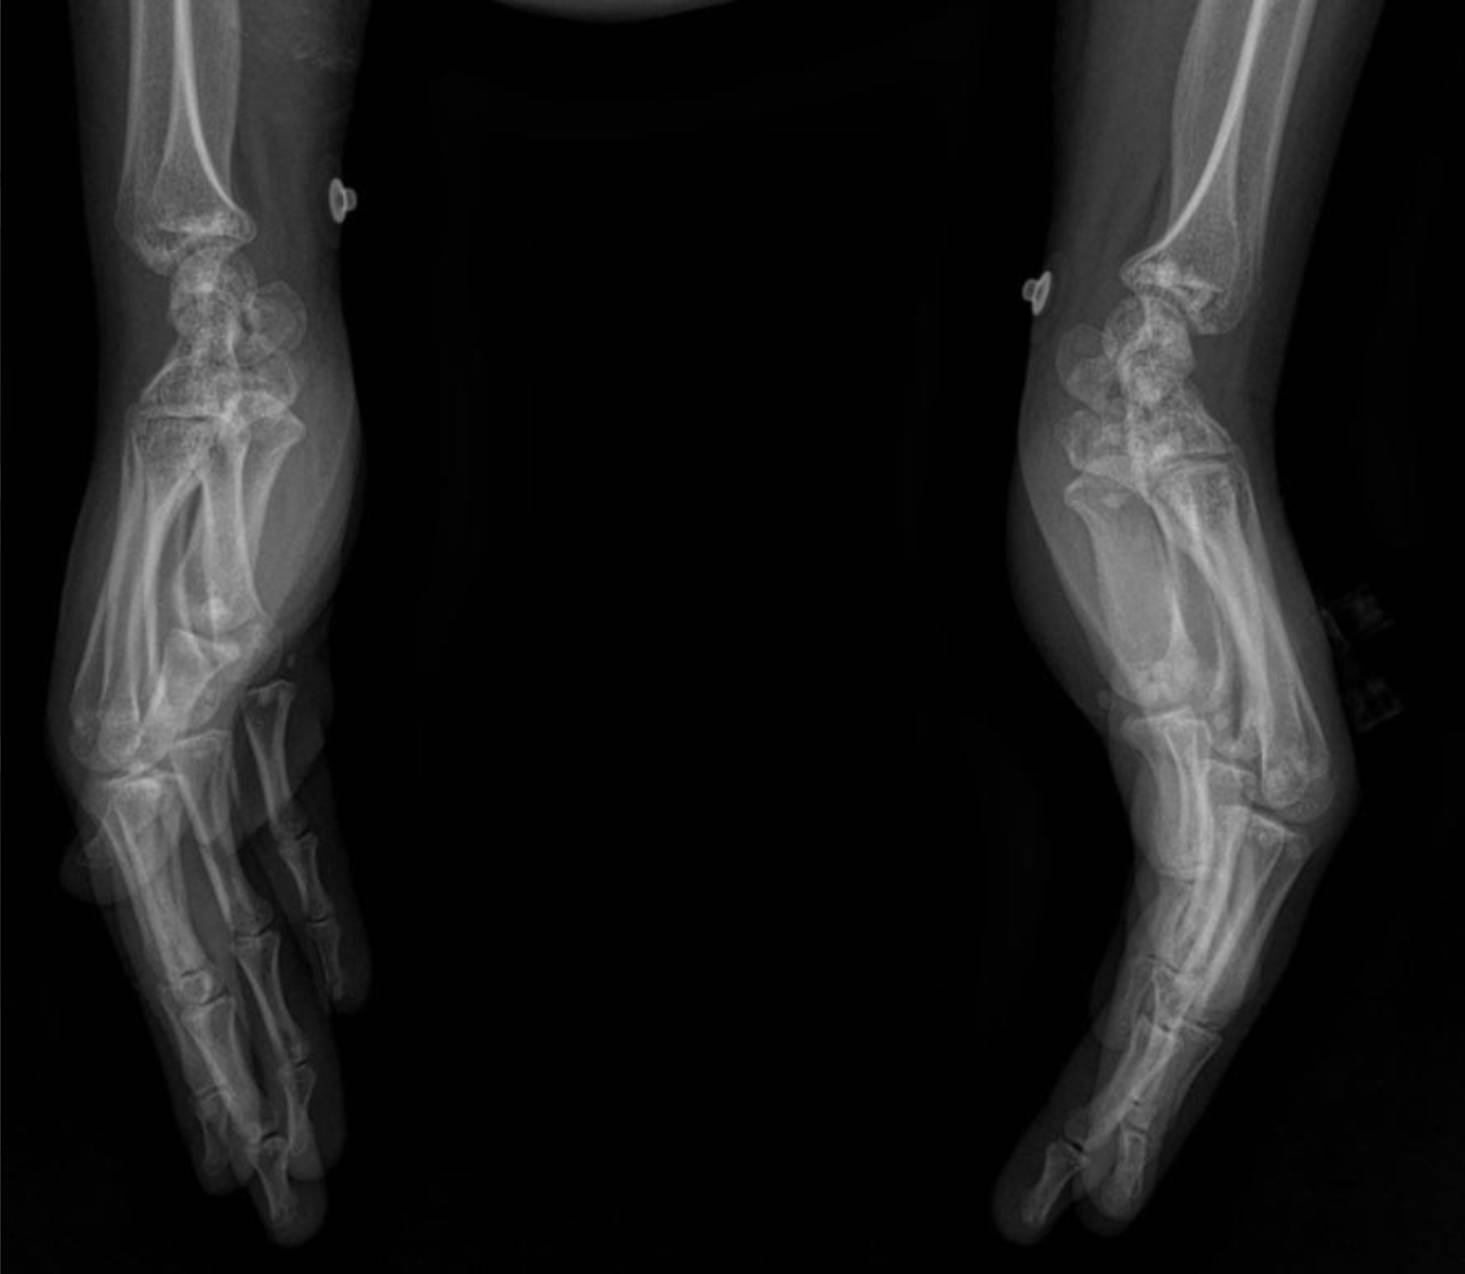

Radiological Findings: Skeletal X-rays (Incidental Discovery)

During the extensive workup for her hypertension and renal issues, skeletal X-rays were performed, which revealed a striking and unexpected finding.

The X-rays of the pelvis, knees, elbows, wrists, and ankles demonstrate multiple, discrete, well-circumscribed sclerotic (densely opaque) lesions distributed symmetrically throughout the bones. These lesions are typically ovoid or spherical, varying in size, and are predominantly located in the epiphyses and metaphyses of long bones, as well as in the carpal and tarsal bones and the pelvic girdle.

- Wrists and Hands: The carpal bones, distal radius and ulna, and to a lesser extent, the metacarpals and phalanges, exhibit multiple small, dense foci.

These widespread, symmetrically distributed sclerotic bone islands are pathognomonic for hereditary osteopoikilosis (also known as osteopathia condensans disseminata). This condition is typically benign and often discovered incidentally. While not directly related to her renal artery stenosis or hypertension, its discovery is crucial for patient management as it can sometimes be associated with other connective tissue disorders, though often it is an isolated finding.